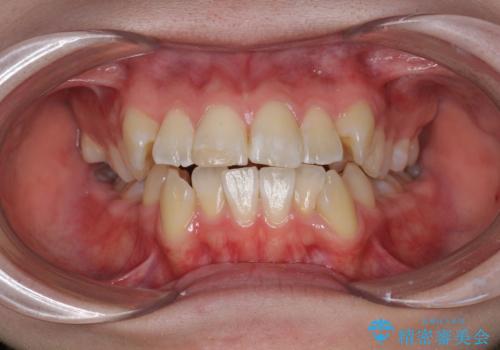

- 歯のデコボコ|口ボコ|八重歯が気になる!|ワイヤー矯正

- 急速拡大装置 狭い骨幅を拡大した上で、口元の突出感を改善する抜歯矯正治療